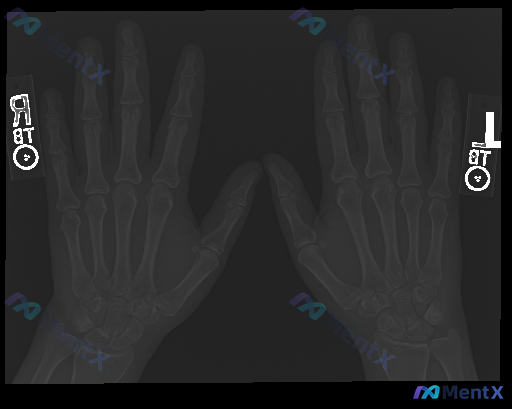

整理到一份双侧手部正位X光片的分析资料,情况有点值得讨论:

影像评估的客观描述是:

- 各掌骨、指骨及腕骨骨皮质连续,未见明确骨折线、骨质破坏或异常硬化;

- 骨小梁走行自然,骨密度尚均匀,未见弥漫性疏松;

- 各关节(CMC、MCP、PIP、DIP)间隙清晰,宽度对称,对位良好,无脱位/半脱位;

- 关节边缘未见明确骨赘或边缘性骨侵蚀;

- 软组织影无明显肿胀,未见明确肿块或异常钙化/异物影。

放射学印象给出的是“未见明显骨性病变,可视为双侧手部骨骼及关节的正常表现”。

但同时存在“存在异常”的提示。

如果仅先看这组信息,大家会觉得这种“分离”的情况,更可能是哪方面的问题?